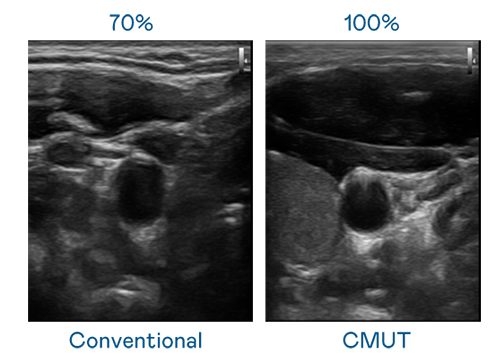

CMUT 技术是一种用电容式微机电元件来产生超音波讯号的技术。与传统 PZT 压电式技术相比,CMUT 频宽增加 30%,更宽频的超音波讯号让影像解析度大幅提升,是实现高影像品质医疗超音波扫描、促进精准医疗发展的关键技术。

超音波影像的解析度高低,首先取决于探头能发出的讯号频宽。XPJ(中国大陆) CMUT 可提供高清晰的超音波讯号,提供高频宽、高灵敏度、影像纹理细节更高的超音波影像,协助医护人员缩短影像判读时间及利用精准的医疗影像进行诊断。